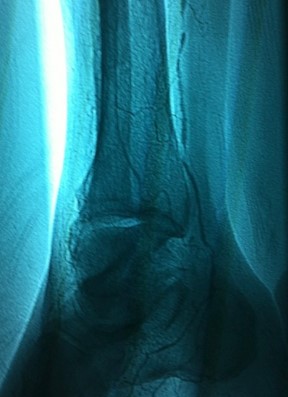

Image

672 Before Restoration

Before restoration of Blood Flow